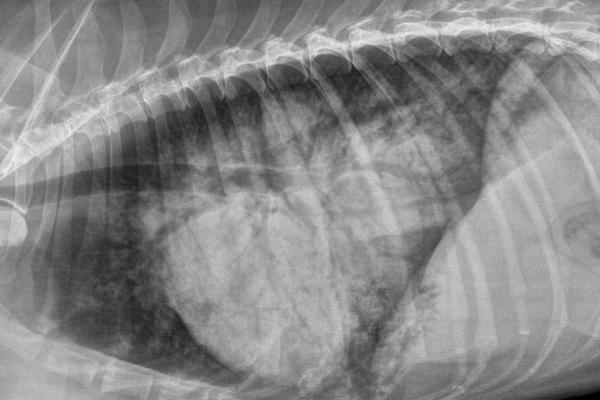

Clase 25: Radiología torácica general 1. Técnica radiológica y principales defectos técnicos. Anatomía radiológica general del tórax (continente y contenido). Principales afecciones del diafragma, pared costal y esternón. Radiología del mediastino: variaciones normales. Principales linfonódulos mediastínicos (craneales, esternal, perihiliares). Linfoadenomegalias. Diagnóstico diferencial de masa pulmonar. Neumomediastino.Información adicional

En la práctica clínica de todos los días, son muchas las especialidades que tienen a la radiología como un pilar del diagnóstico complementario. El método radiológico aporta información sobre la patología osteoarticular de huesos largos, columna y cráneo, enfermedades del aparato digestivo, renal, urinario y reproductor, el sistema respiratorio y cardiovascular.